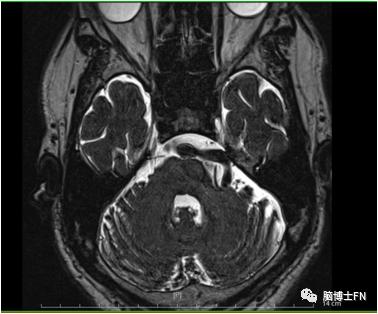

入院查体:神志清楚,血压150/90mmHg,生命体征平稳,病理征未引出。入院后常规检查提示无异常,查头部MRI+3D-TOF提示“椎基底动脉迂曲,左侧椎动脉、基底动脉迂曲增粗并压迫三叉神经根部”,查头部CTA提示“椎基底动脉走形迂曲延长明显增粗,并向左偏移”。

头部MRI+3D-TOF